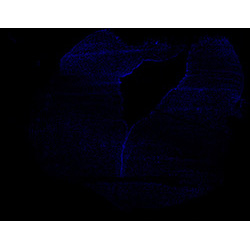

DAPI

6PCW human midbrain